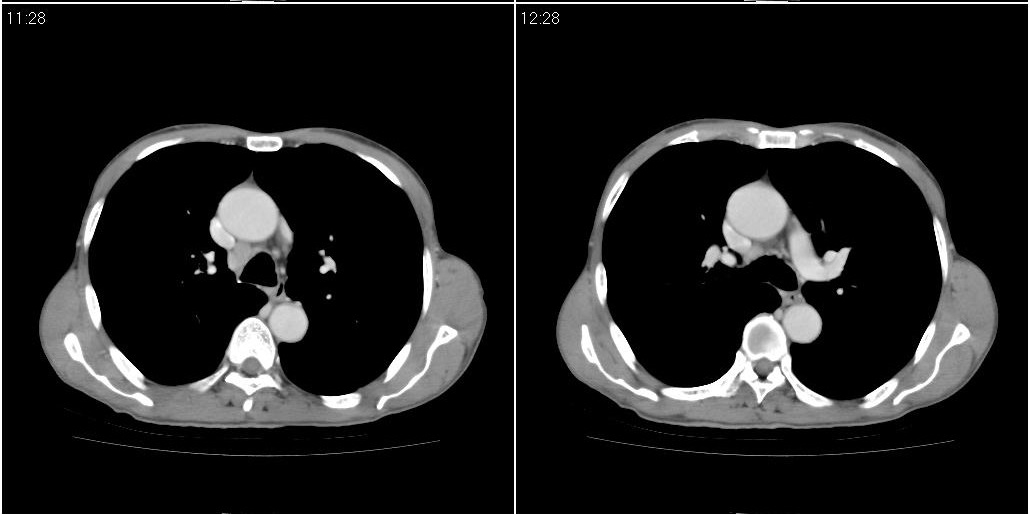

考虑右肺下叶炎症可能性大?未除占位,建议增强。右下肺肺不张

右下胸壁皮下气肿。

右下肺阻塞性肺炎!建议纤支镜!

右肺中叶阻塞性不张及肺炎,高度怀疑支气管占位,建议纤支镜检查!